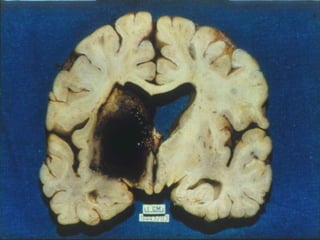

Central nervous system Cerebral infarction in a hypertensive patient is usually attributable to atheroma of one of the larger cerebral arteries (usually the middle cerebral artery) and accounts for about 80 percent of the strokes which these patients suffer.

Intracerebral haemorrhage accounts for 10 to 15 percent,  usually the result of rupture of a small intracerebral degenerative microaneurysm.